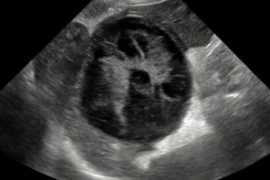

Dr Catheryn Walsh BSc BVSc (Hons) MANZCVS (Radiology) Grad Cert (Hons) (Abdominal Ultrasound)

Dr Catheryn has worked in general practice for 12 years. She received a membership in diagnostic imaging in 2018, has a special interest in internal medicine, and a graduate certificate in abdominal ultrasound. She is currently undertaking post graduate study in cardiology. She runs her own mobile ultrasound business and analyses radiographs for other vets on a regular basis.